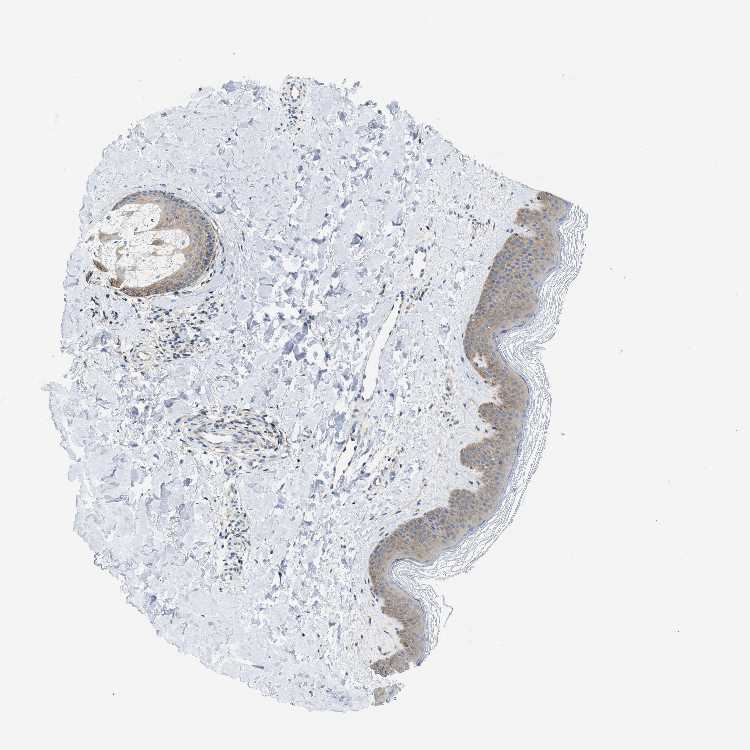

SKIN 2 - Antibody stainingi

Antibody staining in the annotated cell types in the current human tissue is reported as not detected, low, medium, or high, based on conventional immunohistochemistry profiling in selected tissues. This score is based on the combination of the staining intensity and fraction of stained cells.

Each image is clickable and will lead to virtual microscopy that enables deeper exploration of all samples and also displays staining intensity scores, fraction scores and subcellular localization as well as patient and tissue information for each sample.

Antibody HPA029501Antibody CAB019421

Epidermal cells MediumMedium